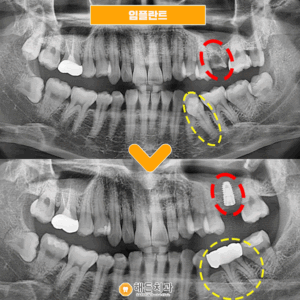

오늘 소개해 드릴 분께서는

오른쪽 아래 사랑니가 불편하셔서

본원을 찾아주셨는데요.

사랑니가 잇몸뼈를 뚫고 나오지 못해

매복되어 있는 상태를 확인할 수 있었으며

주변 잇몸이 자주 붓고 불편하셔서

발치하시길 원하셨습니다.

그런데 해당 사랑니는

아래턱 하방으로 지나는

하치조신경과

비교적 밀접하게 위치해 있었는데요.

발치 과정에서 이 신경을 건드리게 되면

감각 마비 등

여러 가지 부작용이 생길 수 있기 때문에

발치 시 주의를 하여야 한답니다.

♥ 치료 전/후 ♥

(2023.10.12 ㅡ> 2024.2.23)